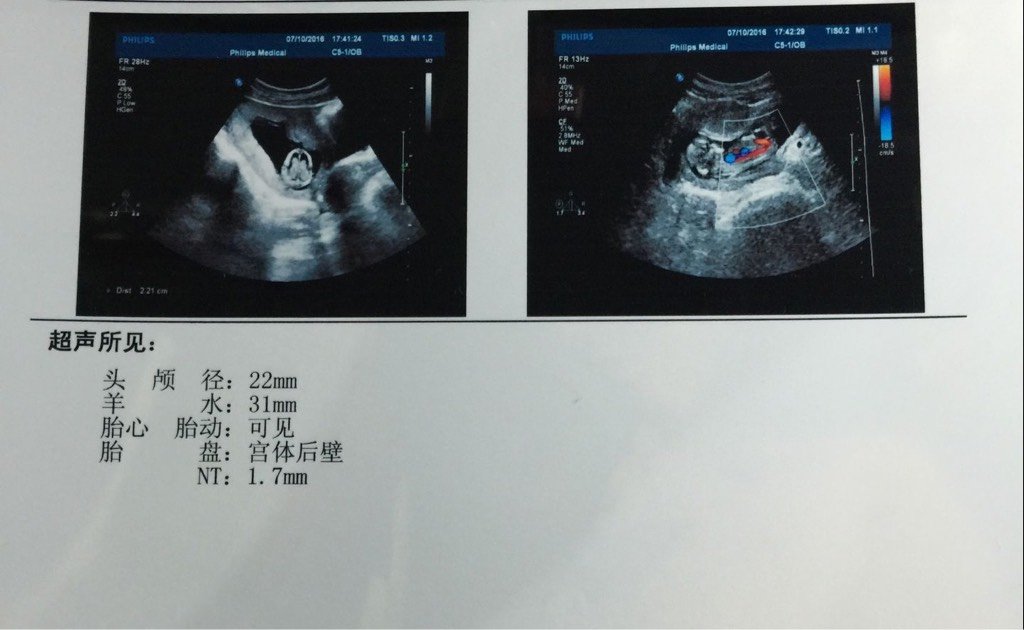

nt:1.7,帮我看看是男孩女孩呢

图片尺寸480x360